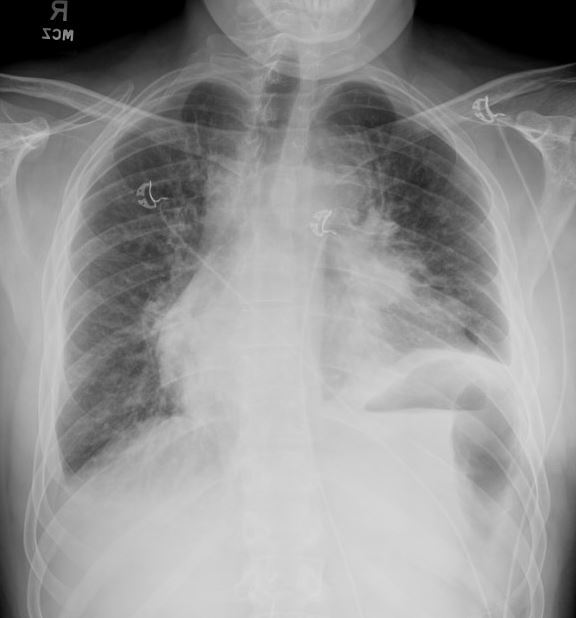

Two months later, he presents to the emergency department with worsening shortness of breath, fatigue, and hoarseness. Bedside echocardiography shows enlarged pericardial effusion, with thickness of 2.65 cm; dilated inferior vena cava without respiratory variation; and partial diastolic collapse of the right atrium and right ventricle. A pericardial drain is placed, and 750 mL of serous fluid is removed from the pericardial space. Approximately 30 minutes after the procedure, the patient becomes increasingly dyspneic and hypoxic, with SpO₂ 83% despite heated high-flow blender oxygen at 100% and 60 L/minute. Venous blood gas analysis shows pH 7.02 and PCO₂ 87 mm Hg. Emergent endotracheal intubation is performed, with exuberant pink frothy secretions seen emanating from the trachea during laryngoscopy. Chest radiographs from before his pericardiocentesis and after his intubation are shown in Figures 5 and 6.

Fig. 6: Chest radiograph following pericardiocentesis and endotracheal intubation.